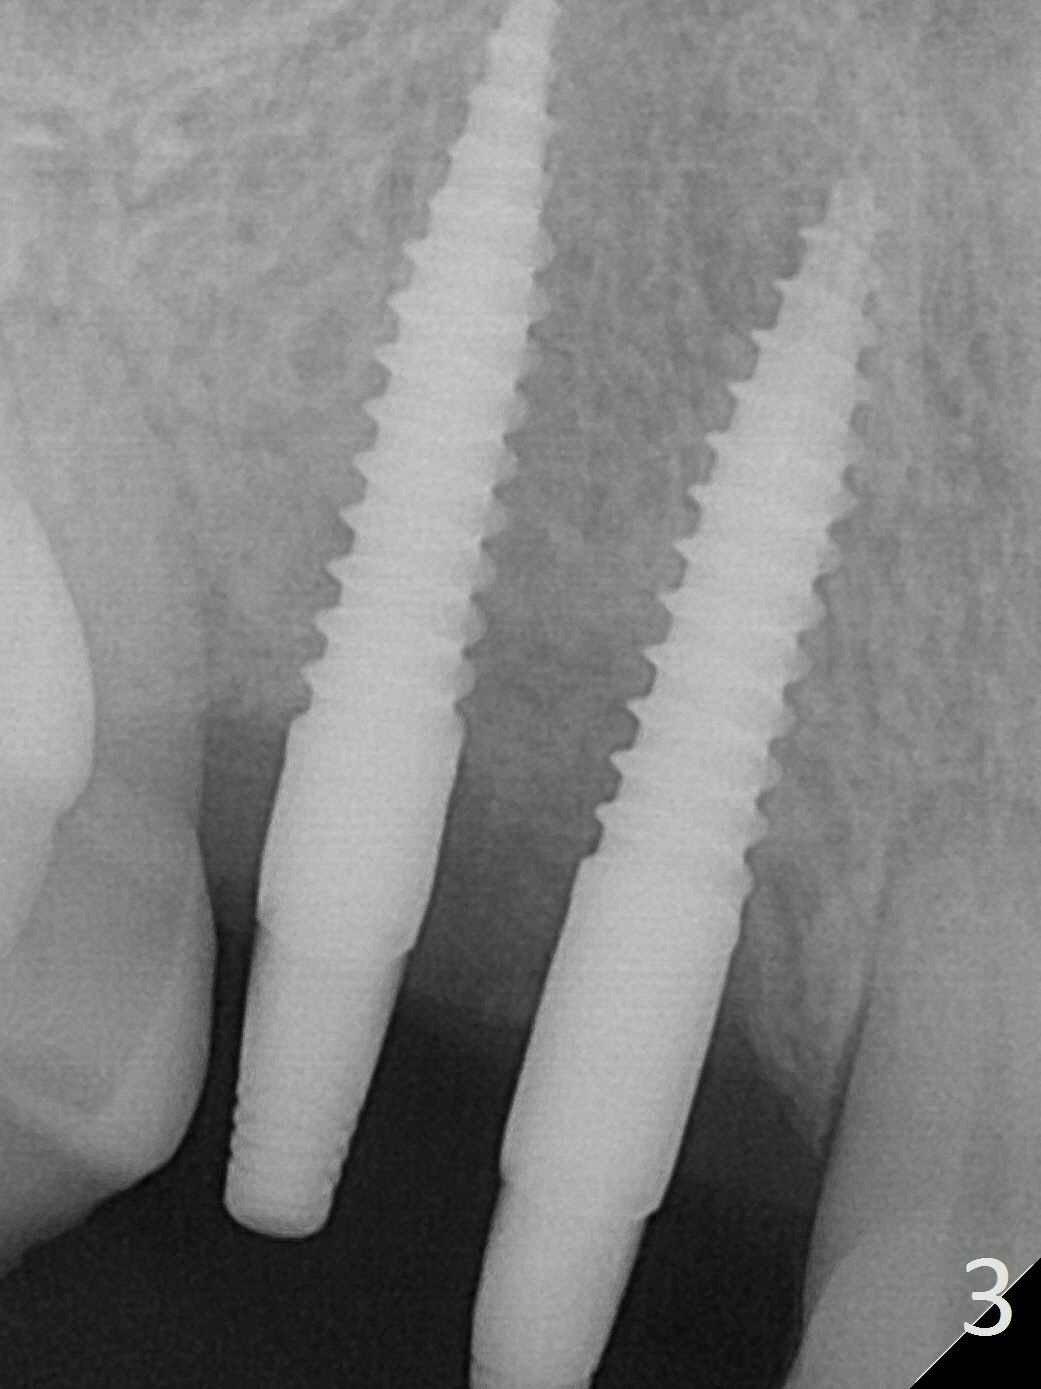

The ridge at the sites of #6 and 7 looks wide, but the bone is narrow (~ 4 mm) when the flaps are raised.  Two of 3 mm 1-piece implants (3x16(2) and 3x14(4) mm) are placed (Fig.1,2).  The other advantage of use of 1-piece implants is the narrow mesiodistal space.  In fact the gingiva is wide and thick (4 mm).  It is ideal to place implants with 4 mm cuff; unfortunately there is no 3x16(4) mm implant available at the site of #6.  After adjustment of the abutment at #7, a splinted provisional is fabricated.

There is no bone loss 3 months postop (Fig.3, probably due to the hard bone).